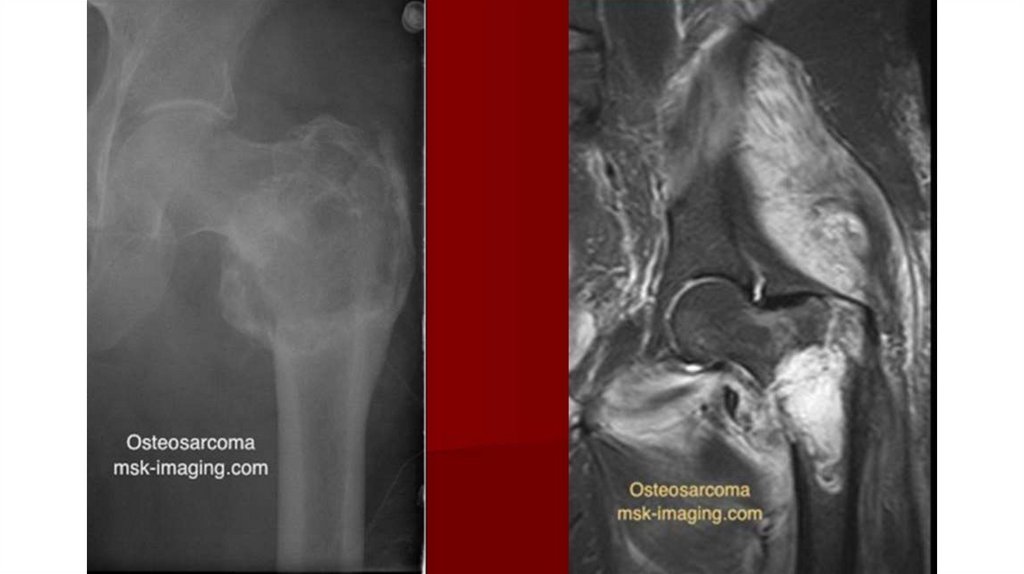

Диагностика

• Рентгенография (очаг деструкции, игольчатый периостит,

«козырек» Кодмана)

• КТ

• МРТ с контрастированием

• Сцинтиграфия с технецием

• Биопсия (высокий полиморфизм с наличием большого количества

митозов, наличие новообразованных остеоидных структур)

• Поиск метастазов